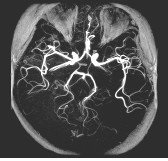

Use the Magnetization Transfer Imaging Option to improve contrast between blood flow and surrounding tissue in 3D TOF images, to augment post-contrast T1-weighted brain images, and to increase myelographic effect for improved disc and cord lesion visualization. This is achieved by saturating tissues containing significant amounts of protein (e.g., gray/white brain matter, skeletal muscle). This is achieved by applying a large saturation pulse that is 1200 Hz off the center frequency.

Spin Echo with a Magnetization Transfer preparation technique can be used to augment post-contrast T1-weighted brain images. Similar to the MRA application, the Magnetization Transfer preparation is used to suppress brain parenchyma signal relative to contrast-laden blood.